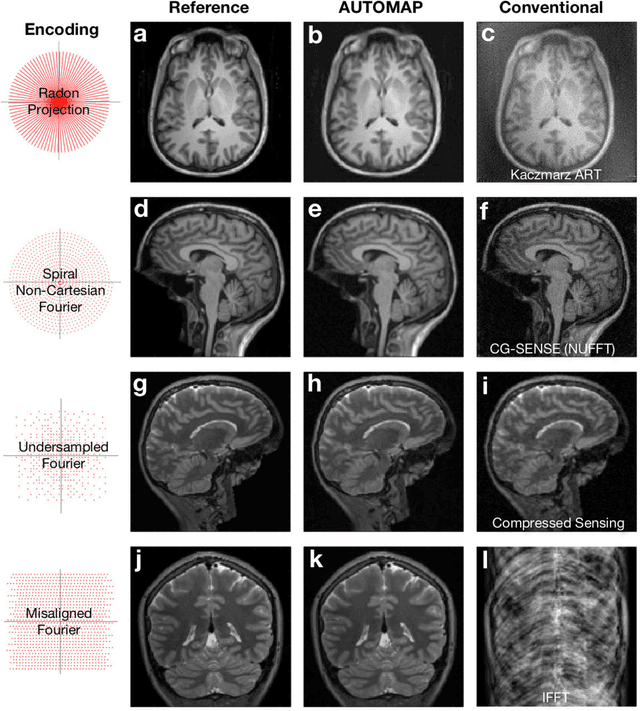

Abstract:Image reconstruction plays a critical role in the implementation of all contemporary imaging modalities across the physical and life sciences including optical, MRI, CT, PET, and radio astronomy. During an image acquisition, the sensor encodes an intermediate representation of an object in the sensor domain, which is subsequently reconstructed into an image by an inversion of the encoding function. Image reconstruction is challenging because analytic knowledge of the inverse transform may not exist a priori, especially in the presence of sensor non-idealities and noise. Thus, the standard reconstruction approach involves approximating the inverse function with multiple ad hoc stages in a signal processing chain whose composition depends on the details of each acquisition strategy, and often requires expert parameter tuning to optimize reconstruction performance. We present here a unified framework for image reconstruction, AUtomated TransfOrm by Manifold APproximation (AUTOMAP), which recasts image reconstruction as a data-driven, supervised learning task that allows a mapping between sensor and image domain to emerge from an appropriate corpus of training data. We implement AUTOMAP with a deep neural network and exhibit its flexibility in learning reconstruction transforms for a variety of MRI acquisition strategies, using the same network architecture and hyperparameters. We further demonstrate its efficiency in sparsely representing transforms along low-dimensional manifolds, resulting in superior immunity to noise and reconstruction artifacts compared with conventional handcrafted reconstruction methods. In addition to improving the reconstruction performance of existing acquisition methodologies, we anticipate accelerating the discovery of new acquisition strategies across modalities as the burden of reconstruction becomes lifted by AUTOMAP and learned-reconstruction approaches.